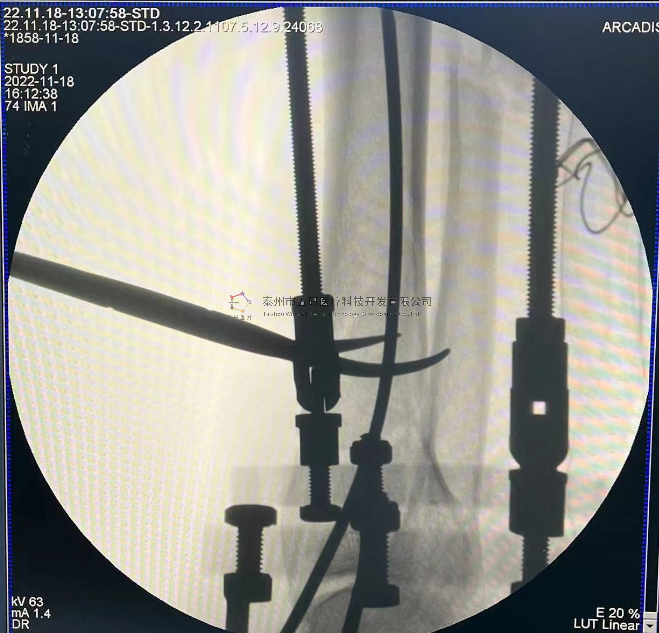

外架馬蹄環(huán)穿過骨針,更方便調整固定角度。